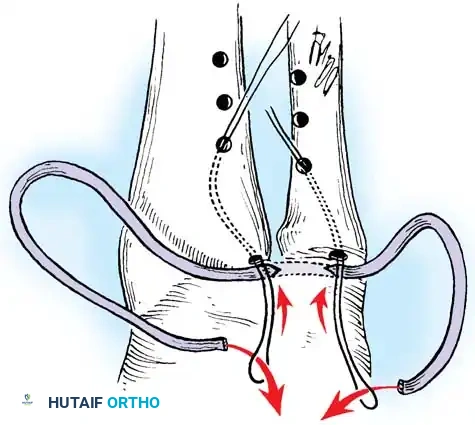

- Pass strong, non-absorbable sutures (e.g., 2-0 FiberWire) through the TFCC using an outside-in or inside-out technique, then shuttle the suture limbs down the osseous tunnels.

The sutures are tied securely over the cortical bone bridge of the ulnar neck, restoring tension to the radioulnar ligaments.

- Tie the sutures over the ulnar cortical bridge with the forearm in neutral rotation to restore anatomic tension.

In cases of severe instability or concomitant ECU subsheath disruption, open capsular repair and ECU stabilization are required.

Open repair of the dorsal capsule and TFCC, ensuring robust closure and stabilization of the ulnar-sided structures.

Stabilization of the ECU tendon and subsheath, a critical step in addressing complex ulnar-sided wrist trauma.